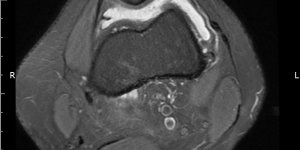

Lipoma Arborescens | Cases

(2016) Patient (male) aged 44 attends physical therapy department with right knee pain. He gives a 5 year history of knee pain. He has noticed on and off swelling in the right knee. The clinician notices high BMI. On knee exam, there is slight swelling noticed on the knee. ROM is full with slight tightness at end range flexion and extension. [...] Read more